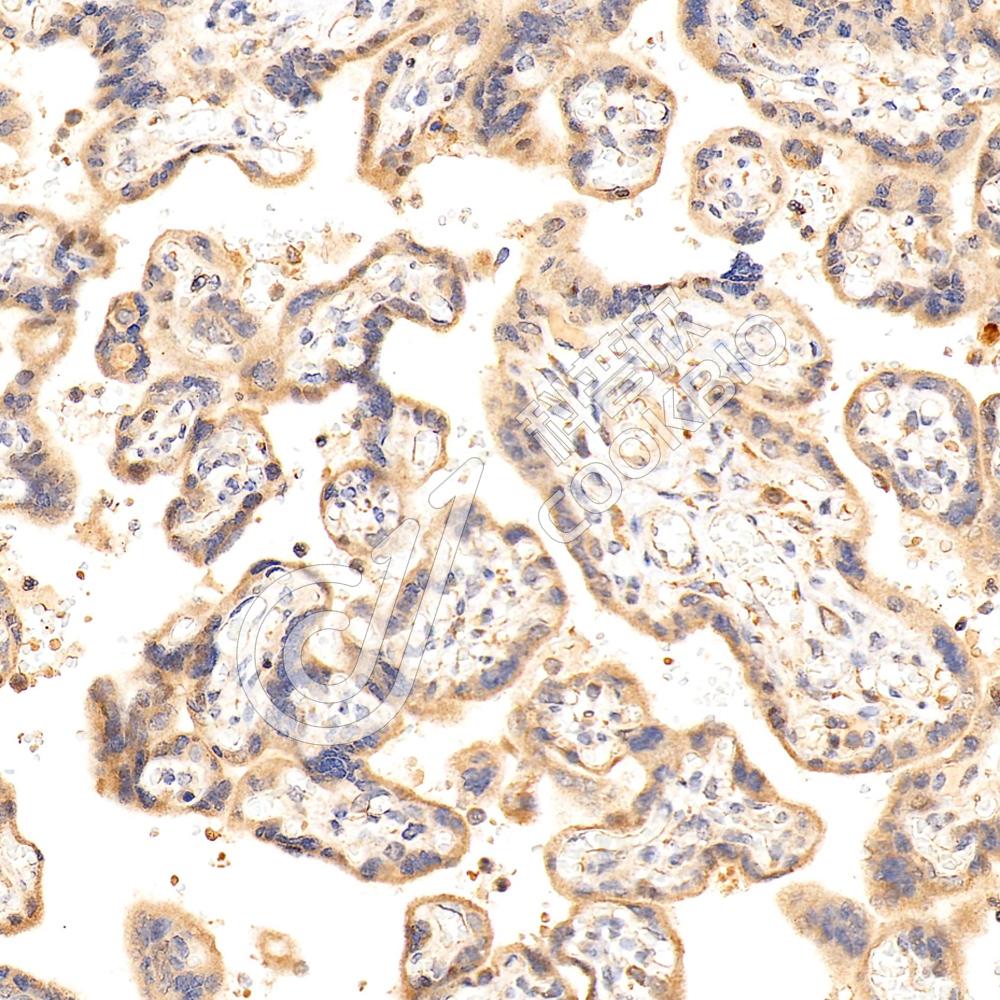

IHC检测Serum Response Factor SRF蛋白(货号 K1333144).

样品: 人胃癌, 4%多聚甲醛 (货号KSG1101) 固定12-24小时.

抗原修复: 柠檬酸抗原修复液(干粉, pH 6.0) (KSG1201), 98℃, 20分钟.

—抗: 1: 1800稀释, 4℃ 孵育过夜.

二抗: S-vision免疫组化多聚二抗(山羊抗兔),即用型 (货号KB3906), 室温孵育20分钟.